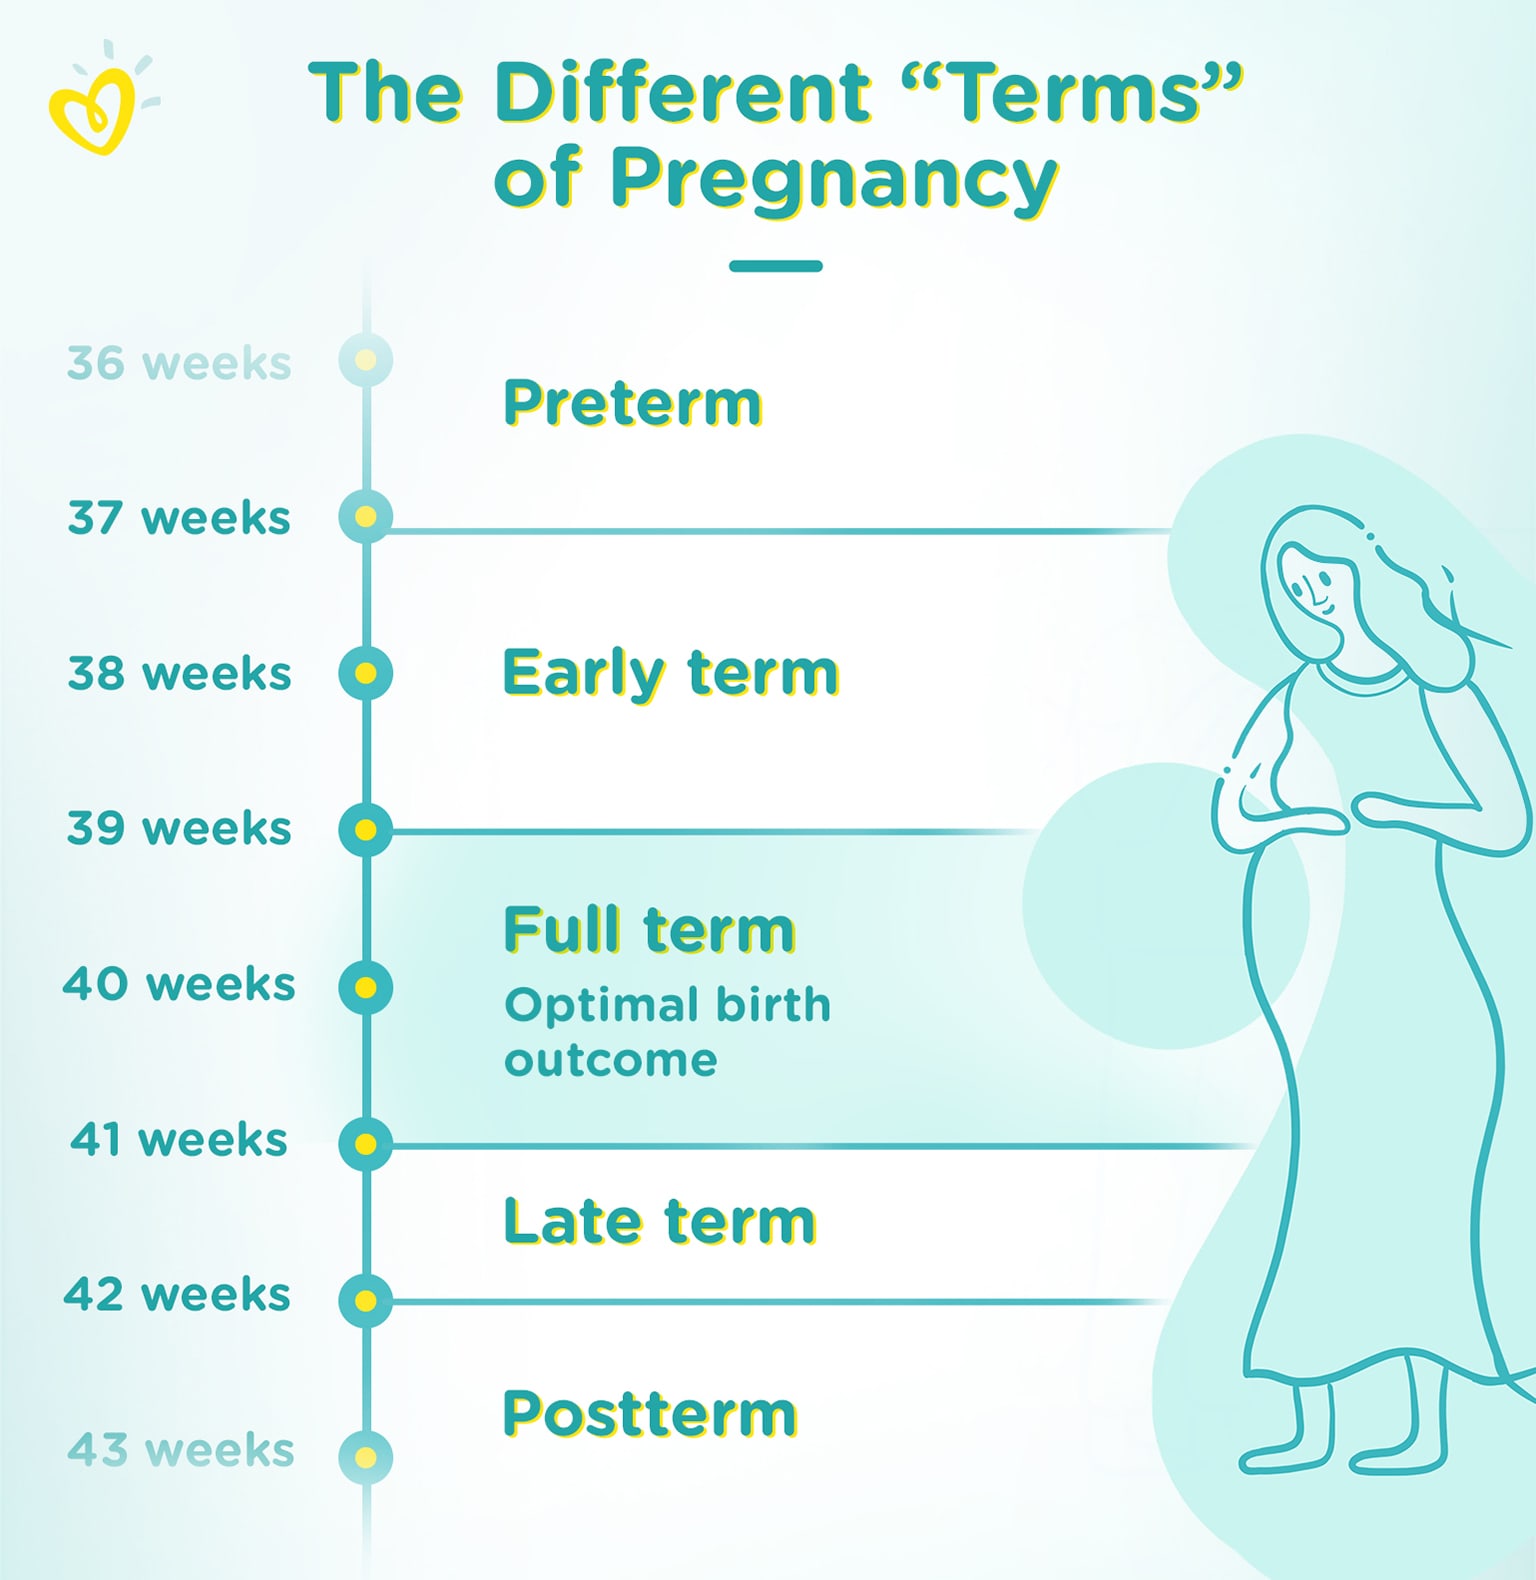

The Best How Many Weeks Pregnant Is Considered Full Term Ideas …

Full Term Pregnancy 36 Weeks / Quick Answer Is Baby Fully Developed At …

How Many Weeks Are In A Full Pregnancy – PregnancyWalls